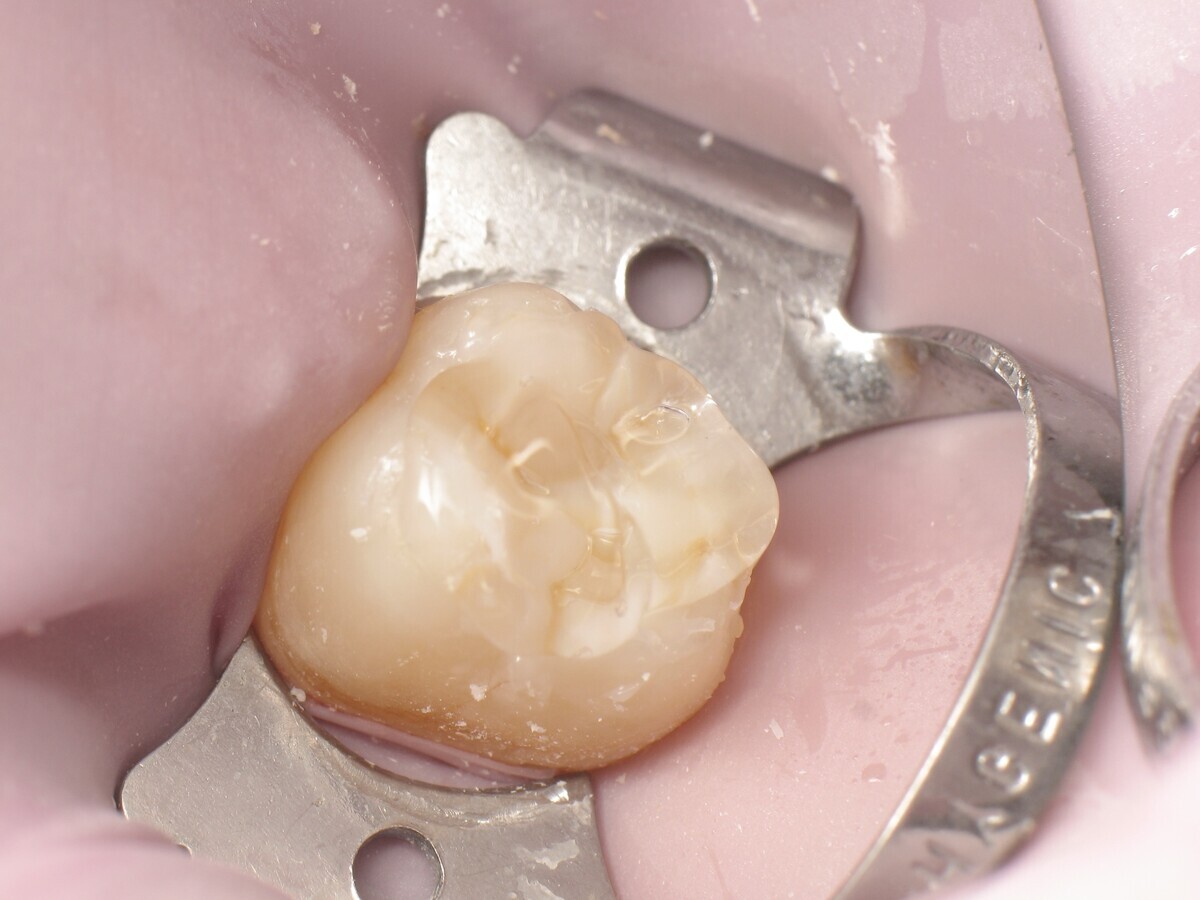

Este artículo describe el tratamiento de una cavidad clase I en un molar utilizando un composite termoviscoso mediante la técnica de la almohadilla (Figura 1). En primer lugar, se registran los detalles anatómicos utilizando una resina transparente, fluida y fotopolimerizable (Clip Flow, VOCO). El diente se aísla con un dique antes de aplicar el composite transparente a la superficie oclusal con un cepillo aplicador y fotopolimerizar durante 10 segundos (Figuras 2-4). La almohadilla oclusal así obtenida (Figura 5) debe almacenarse en alcohol (etanol o isopropanol) para eliminar la capa de inhibición. Luego se limpia la cavidad clase I (Figuras 6 y 7). A continuación se graba el esmalte durante 30 segundos y la dentina durante 15 segundos (Conditioner 36, Dentsply Sirona) y luego se enjuaga bien (Figuras 8 a 10). Debido al bajo espesor de la dentina remanente, también se aplica protección pulpar (Telio Desensitizer, Ivoclar Vivadent) (Figura 11). Luego se frota el adhesivo sobre las superficies dentales durante 20 segundos (Futurabond DC, VOCO), luego se seca bajo una pulverización de aire sin aceite graso durante 5 segundos y luego se fotopolimeriza durante 10 segundos (Figuras 12, 13). Para una humectación óptima, el fondo de la cavidad se cubre con un compuesto fluido de baja viscosidad (GrandioSO Light Flow, A3.5, VOCO) y se fotopolimeriza durante 20 segundos (Figuras 14, 15). Utilizando el Dispensador VisCalor, un dispensador portátil que permite el calentamiento y la aplicación simultánea de resinas, la cavidad se llena luego con un composite termoviscoso bulk (VisCalor Bulk, A2, VOCO).

El composite calentado tiene una consistencia fluida para un perfecto manejo y se puede aplicar en capas de hasta 4 mm (Figura 16). A medida que se enfría hasta la temperatura corporal, la viscosidad del composite termoviscoso aumenta, lo que lo hace muy fácil de modelar (Figura 17). Finalmente, se realiza la fotopolimerización durante 20 segundos (potencia ≥ 1.000 mW/cm2, Figura 18). El uso de un composite bulk permite un llenado rápido en un solo paso. Si se requiere una segunda capa, la capa superior también se puede realizar con composite termoviscoso estético universal VisCalor en color A1 (VisCalor, VOCO, Figura 19), que se fotopolimeriza en incrementos de 2 mm. La consistencia innovadora del composite termoviscoso permite una reproducción fácil de la anatomía y una eliminación fácil del exceso de material (Figura 20) [Ilie et al. 2014]. A continuación se aplica la almohadilla oclusal creada previamente (Figura 21). La fotopolimerización se realiza primero con la almohadilla y luego sin durante 20 segundos cada una (Figuras 22 a 24). No se requiere material separador entre el material compuesto y la almohadilla. Debido a la eliminación previa de la capa de inhibición de la almohadilla, hay muy pocos o ningún punto de contacto, de modo que no se puede crear ningún enlace químico real entre la almohadilla y la resina. Los pocos puntos de contacto presentes solo significan que puede sentir una ligera resistencia cuando se retira la almohadilla después del primer ciclo de fotopolimerización.

Figura 19. Aplicación de VisCalor.

Figura 20. Eliminación de excesos.